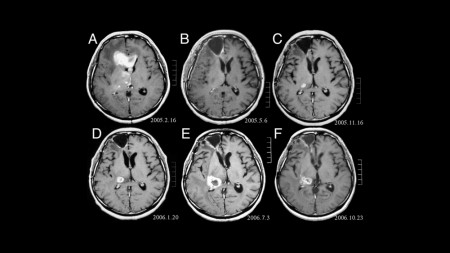

Imagens do cérebro produzidas por ressonância magnética funcional. Software permite reconhecer diferenças sutis entre as estruturas classificadas como normais e as que caracterizam os portadores de esquizofrenia (imagem:Acervo do pesquisador)

No mapeamento já realizado, as imagens foram obtidas por meio de ressonância magnética funcional e o cérebro foi mapeado como uma rede complexa. Cada vértice da rede representa uma área cortical. As diversas áreas são ligadas de acordo com a ativação durante o experimento. Essa rede foi analisada computacionalmente com o uso de descritores estatísticos e métodos de mineração de dados. Tais análises evidenciaram que existem diferenças sutis, mas bastante definidoras, entre os dois tipos de estruturação cortical, ou seja, a estrutura do cérebro das pessoas classificadas como normais e aquela dos portadores de esquizofrenia.

Segundo o pesquisador, a diferenciação das redes corticais não poderia ter sido realizada por observadores humanos, mesmo que fossem especialistas na área, porque, visualmente, as redes são muito parecidas, apresentando diferenças de estruturação mínimas. “Por meio da mineração computacional de dados, a separação das imagens em dois conjuntos distintos pôde ser feita em minutos, por computadores pessoais comuns. Extraímos 54 medidas das redes corticais e apenas quatro se mostraram relevantes para realizar a classificação dos indivíduos”, complementou.